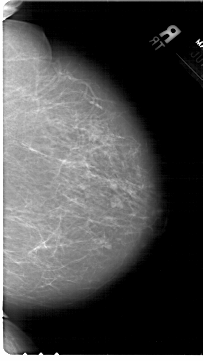

ics_version 1.0 filename A-1567-1 DATE_OF_STUDY 7 6 1995 PATIENT_AGE 44 FILM FILM_TYPE REGULAR DENSITY 2 DATE_DIGITIZED 2 10 1998 DIGITIZER HOWTEK 43.5 SEQUENCE LEFT_CC LINES 6871 PIXELS_PER_LINE 3841 BITS_PER_PIXEL 12 RESOLUTION 43.5 OVERLAY LEFT_MLO LINES 6871 PIXELS_PER_LINE 4051 BITS_PER_PIXEL 12 RESOLUTION 43.5 OVERLAY RIGHT_CC LINES 6841 PIXELS_PER_LINE 3841 BITS_PER_PIXEL 12 RESOLUTION 43.5 NON_OVERLAY RIGHT_MLO LINES 6871 PIXELS_PER_LINE 3781 BITS_PER_PIXEL 12 RESOLUTION 43.5 NON_OVERLAY |